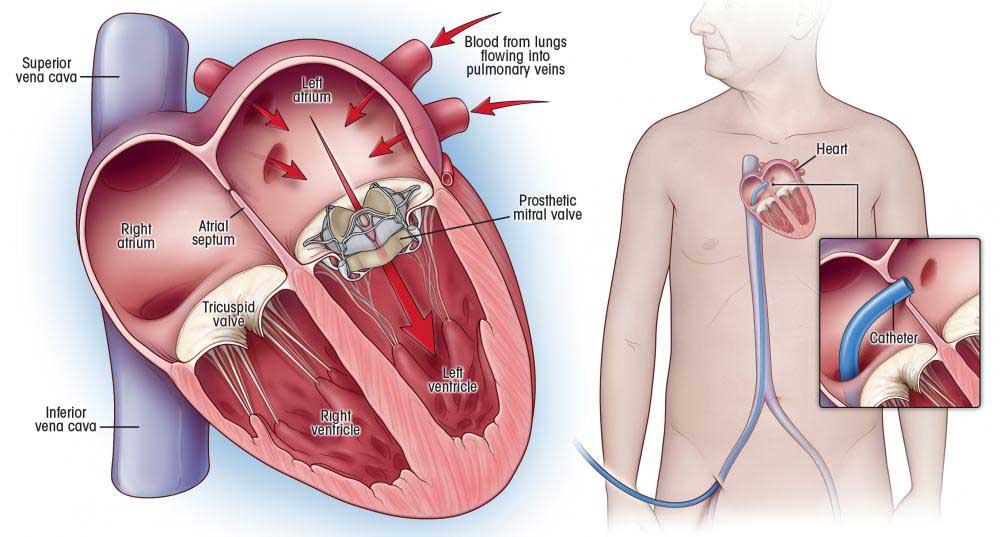

Overview

Package includes:

Days in hospital : 7 to 8 Days (For patient and one attendant)

Days in hotel : 12 Days (For patient and one attendant)

Room type in hospital : Shared

Room type in hotel : Private

Hotel category: General

Value added benefits of the Mitral Valve Replacement:

Ø Doctor consultation charges

Ø Lab tests and diagnostic charges

Ø Room charges inside hospital during the procedure

Ø Surgeon Fee

Ø Cost of implant

Ø Nursing charges

Ø Hospital surgery suite charges

Ø Anesthesia charges

Ø Routine medicines and routine consumables (bandages, dressings etc.)

Ø Food and Beverages inside hospital stay for patient and one attendant.

Extra benefits:

ü Interpreter

ü Visa assistance

Ø Site tourism of the city

Ø Follow up with the doctor

Ø Airport pick up and drop

Ø Free online consultation with the doctor

Ø Priority appointments with the doctor

Ø Room upgrade from sharing to private